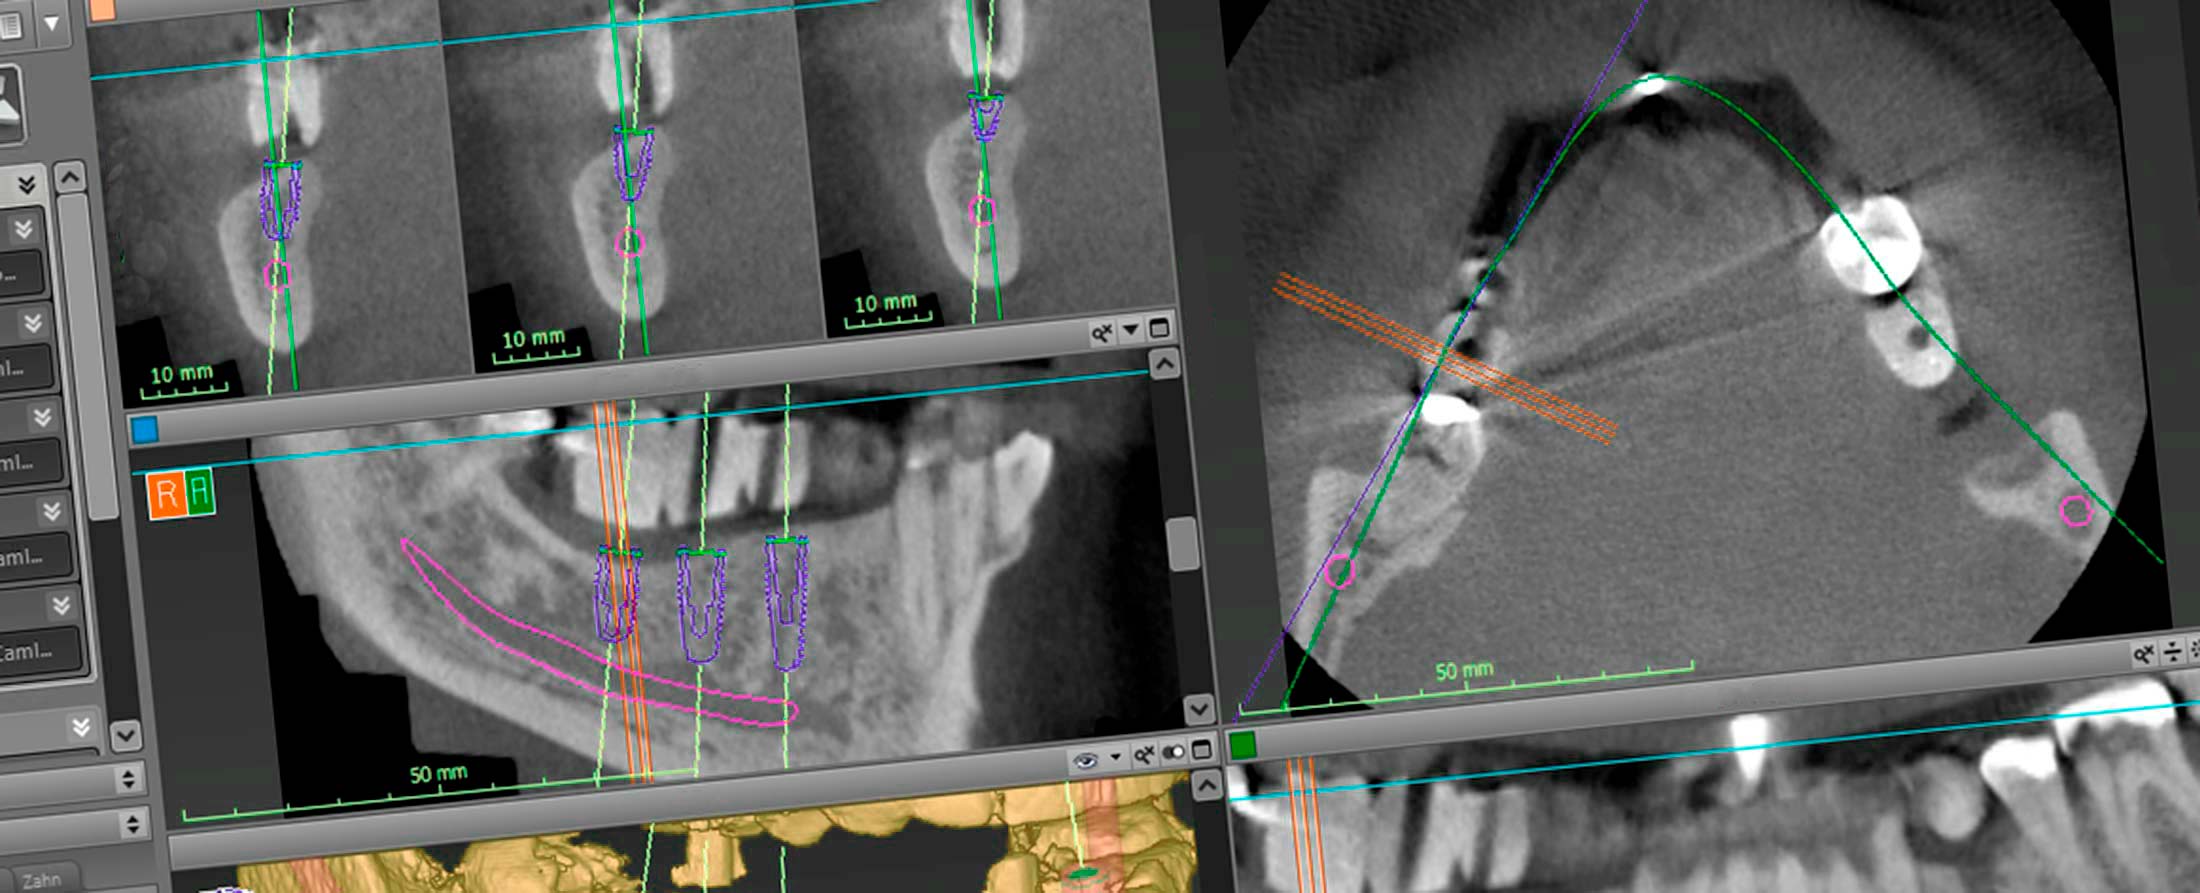

Erstklassige und umfassende Diagnosen. Mit den gestochen scharfen 3-D-Ansichten können wir ausgesuchte, einzelne Segmente oder komplexe Zusammenhänge der knöchernen Strukturen des Oberkiefers und des Unterkiefers detailliert darstellen. Die Digitale Volumentomographie ermöglicht zusammen mit unserer Implantationssoftware eine computergestützte 3D-Planung, die in der Implantologie eine besonders schonende Vorgehensweise ermöglicht. Sie unterstützt uns bei der Planung, der Auswahl eines geeigneten Implantat-Designs und der optimalen Implantat-Position. Unsere überweisenden Kollegen erhalten schon in der Planungsphase wichtige Informationen für eine bessere prothetische Versorgung von Implantaten. Digitale Volumentomographie bietet dem Behandlerteam den aktuell sichersten und höchsten Standard in der Röntgendiagnostik.

Die Darstellung von Hochkontraststrukturen und deren komplexen Analysen (Nervverlauf, Knochenbreite, räumliche Abbildung anatomischer Strukturen) ermöglichen in der Medizin eine neue Qualität in der Diagnostik und Planung. Unsere Patienten profitieren vom erhöhten medizinischen Standard durch mehr Transparenz in der Diagnostik und Planung sowie erhöhter Sicherheit in der Umsetzung und Kontrolle.